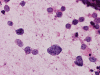

A. Squash |

B. Squash |

C. Squash |

D. Squash |

The cytologic preparation demonstrates scattered to small clusters of small blue cells with a "dirty background" (Panel A). In general, the nuclei are round to oval and with a hyperchromatic, coarse salt and pepper like nucleoplasm. Many cells with pyknotic or apoptotic appearing nuclei are noted (Arrows in Panel A and B). A large, prominent nucleoli can be seen in many tumor cells (Arrow in Panel C). There is also large variation of tumor size (Panel D). The histopathologic picture of frozen sections (Panel D and E) is consistent with a small blue cell tumor. Note that the the nuclear details is poorly preserved. In general, nuclei of small blue cell tumors are much better demonstrated on cytologic preparation than frozen section. The frozen section, however, gives the overall architecture of the tumor.